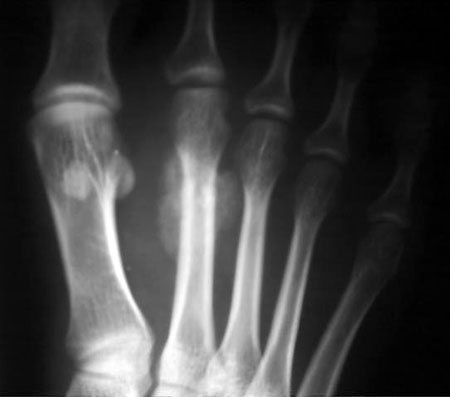

女,28岁,自觉右足局部疼痛近一月,局部肿大,皮温不高,无明确外伤史。

多考虑第2足掌骨疲劳骨折伴修复骨枷或骨化性肌炎。

第2足掌骨行军骨折(即疲劳骨折)

特点:1、好发于第二跖骨骨干远端, 2、骨折后仍能行走, 3、常在骨折后2~3周后就诊, 4、骨折线多不明显,周围有小丘状骨膜新生骨。

28岁的女性,那能走了这么多的路,认为疲劳性骨折可能极小。该病例软组织肿胀明显,结合病史考虑:皮质旁骨肉瘤或骨膜肉瘤。

第2跖骨中、远段交界处内、外侧均可见高密度,但未见骨质破坏,偶考虑疲劳性骨折,女性是否舞蹈爱好者?

支持以上的诊断:特定的好发部位,没有骨质结构的破坏,骨皮质完整,可以和肿瘤相鉴别。建议必要时行ct扫描可能发现隐秘的骨折线。

请见指骨骨折ct矢状面重建图象观察骨折细节:

第一眼的确很像疲劳骨折,但仔细观察发现:病变主要位于骨皮质周围,骨皮质、骨髓腔未见明显改变;疲劳骨折仔细观察一般骨皮质隐约可见透亮线影,透亮线周围骨质增生,形成与骨干垂直的横行致密带状影,一般较规则范围不太大;另外病史非常重要,病人年轻女性,劳累行走可能性不大;所以考虑皮质旁或软组织内病变可能性大。

此例改变为骨周包绕骨密度影,与骨干皮质间隐约示一透亮线影,骨皮质稍增厚。软组织未见明显肿胀。多考虑为表面骨肉瘤,又以皮质旁骨肉瘤可能性大;疲劳骨折后骨痂可能性极小。

第2跖骨中段见骨皮质硬话,骨膜反应.外侧见稍高密度影.

右足第二跖骨远段周围骨痂样密度阴影,边缘清楚,骨皮质边缘欠光滑,未见明显骨折线及硬化带,无明显软组织肿块。符合皮质旁骨肉瘤的影像学表现,该部位虽是疲劳骨折的好发部位,临床除应有明确过度活动史外,影像学应有骨折线或由内骨痂形成的硬化带。